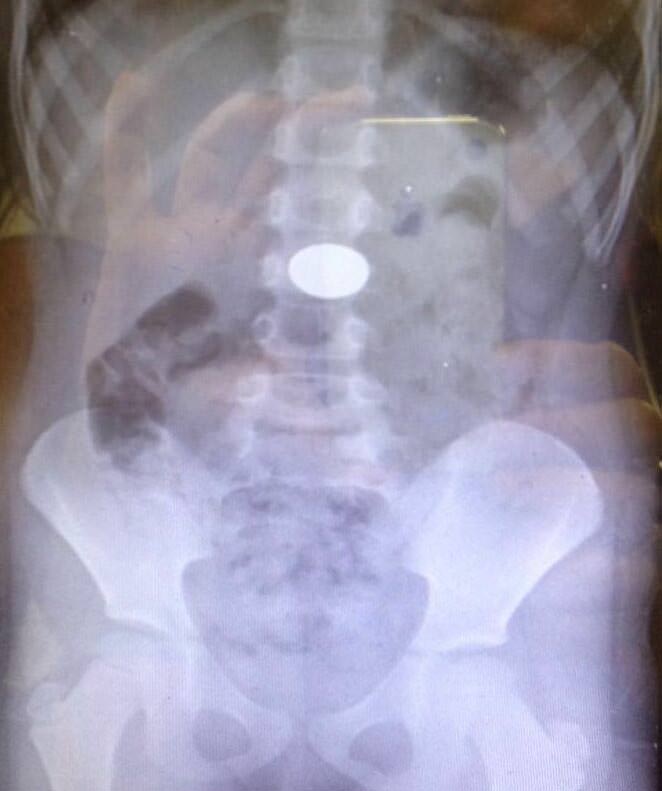

Bu objelerden en tehlikelisinin piller olduğuna dikkat çeken Doç.Dr. Maşallah Baran, "Piller kimyasal mekanizmayla mukozayı yakıyor, özellikle yemek borusu çok duyarlı pillere, hele ki yeni takılmış bir pilse saatler içinde şahit olduğum bir kaç vaka var, yemek borusunu kömür haline getirebiliyor" dedi.

"Çocukların nefes ve borusu ile midelerinden çıkartılan, anahtarlık, madeni para, saat pili, ataç, çengelli iğne ve çivi gibi objeler görenleri şaşkına çevirdi. "